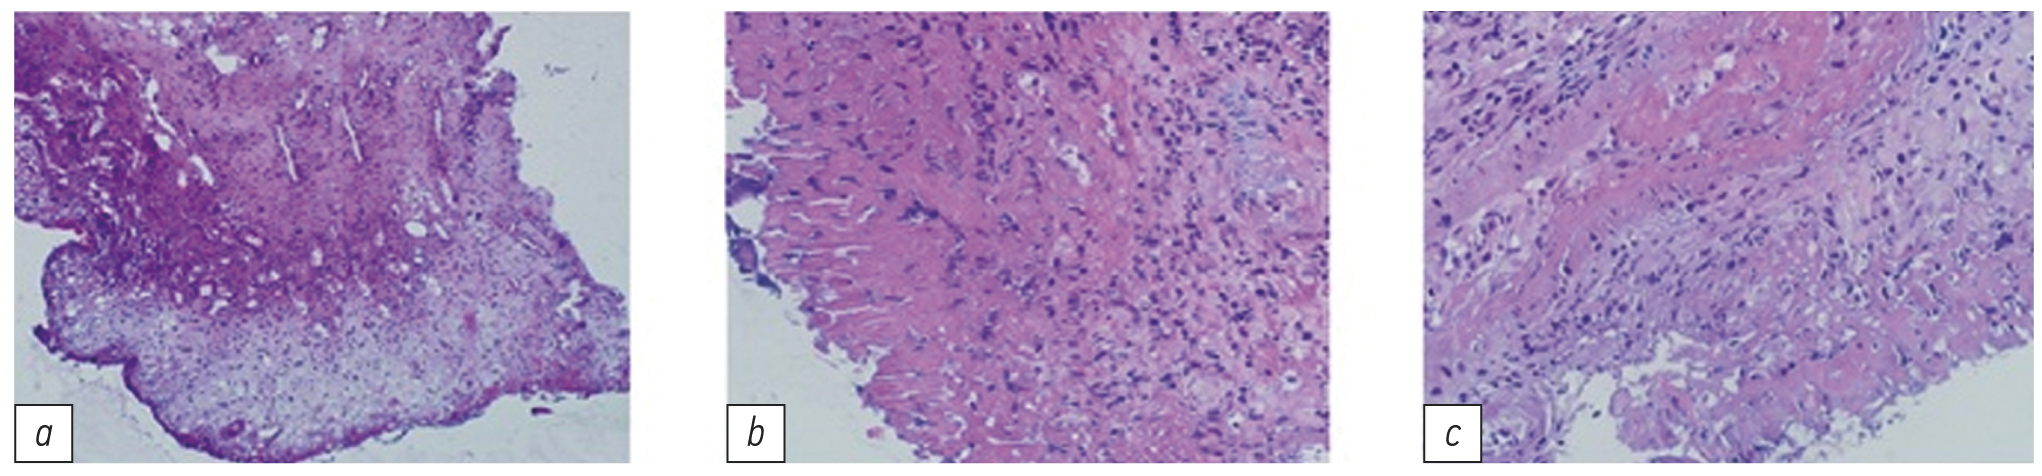

Созревающая грануляционная ткань замещала собой очаги фибриноидно-некротических изменений. В контрольной группе на фоне стандартной терапии морфологическая картина в те же сроки медленно и постепенно переходила в фазу структуризации: просматривались грануляции, однако более вялые и скудные, чем в основной группе. Отмечена очень слабая краевая эпителизация, сохранялись зоны некроза и микроциркуляторных расстройств (рис. 5).

Рис. 5. Гистология края декубитальной язвы (контрольная группа): a — 1-е сутки, ×300; b — 14-е сутки, ×400; c — 28-е сутки, ×400.

Fig. 5. Histology of the edge of the decubital ulcer (control group): a — day 1, ×300; b — day 14, ×400; c — day 28, ×400.